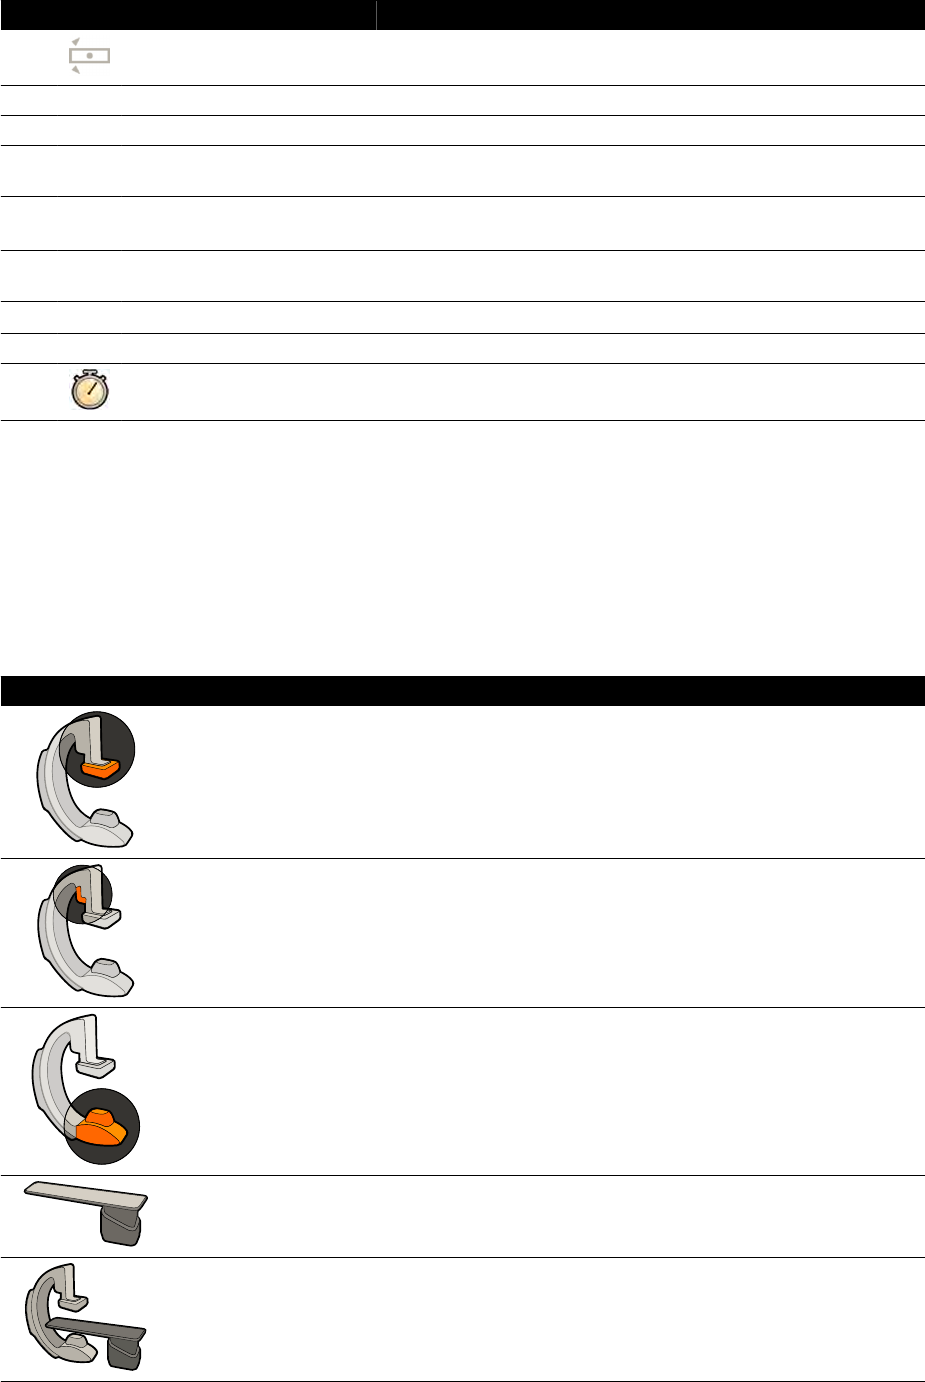

18.8 Moduł sterujący................................................................................................................... 355